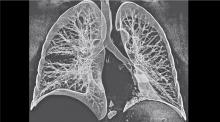

A 57-year-old female patient, with a 10-year history of recurrent and frequent bronchopulmonary infections due to bronchiectasis, experienced nine months of continuous hemoptysis. The patient’s chest physician referred her to the authors’ department for surgical resection of the diseased left lower lobe of the lung.

A single incision VATS (SIVATS) left lower lobectomy was performed through a 3.5 cm incision over the 6th intercostal space in the midaxillary line. The pulmonary artery branches and veins were dissected and stapled without encircling them with a silk suture.